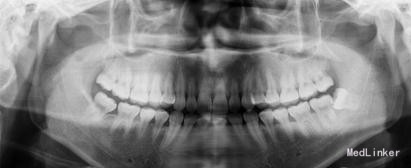

患者,男,25岁,要求拔除左下颌水平阻生牙齿,平素体质一般,无药物、食物过敏史,无高血压、心脏病等系统病史

行曲面断层片